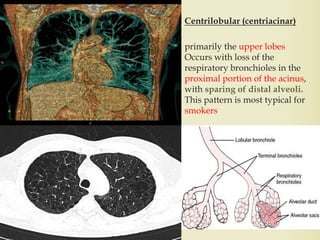

Centrilobular (centriacinar)

primarily the upper lobes

Occurs with loss of the

respiratory bronchioles in the

proximal portion of the acinus,

with sparing of distal alveoli.

This pattern is most typical for

smokers